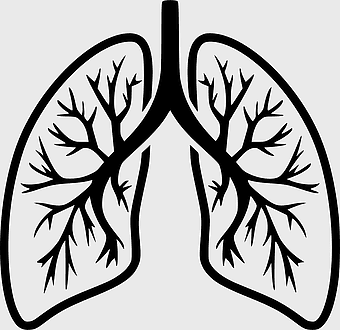

human lungs icon, monochrome lung illustration, breathing organ diagram, anatomy line art, pulmonary tree structure, respiratory system graphic, black and white organ depiction -